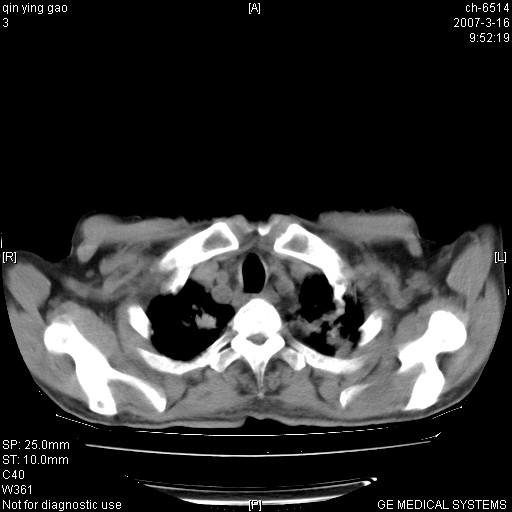

男,64岁.乏力2个月,畏寒、发热1月余。体重下降。血沉加快,白细胞不高。

3.主动脉弓.冠状动脉钙化形成

两肺弥漫分布的斑片状影,部分融合,左肺及纵隔淋巴结见钙化影,考虑1。tb,2。肺泡细胞癌,建议查痰检